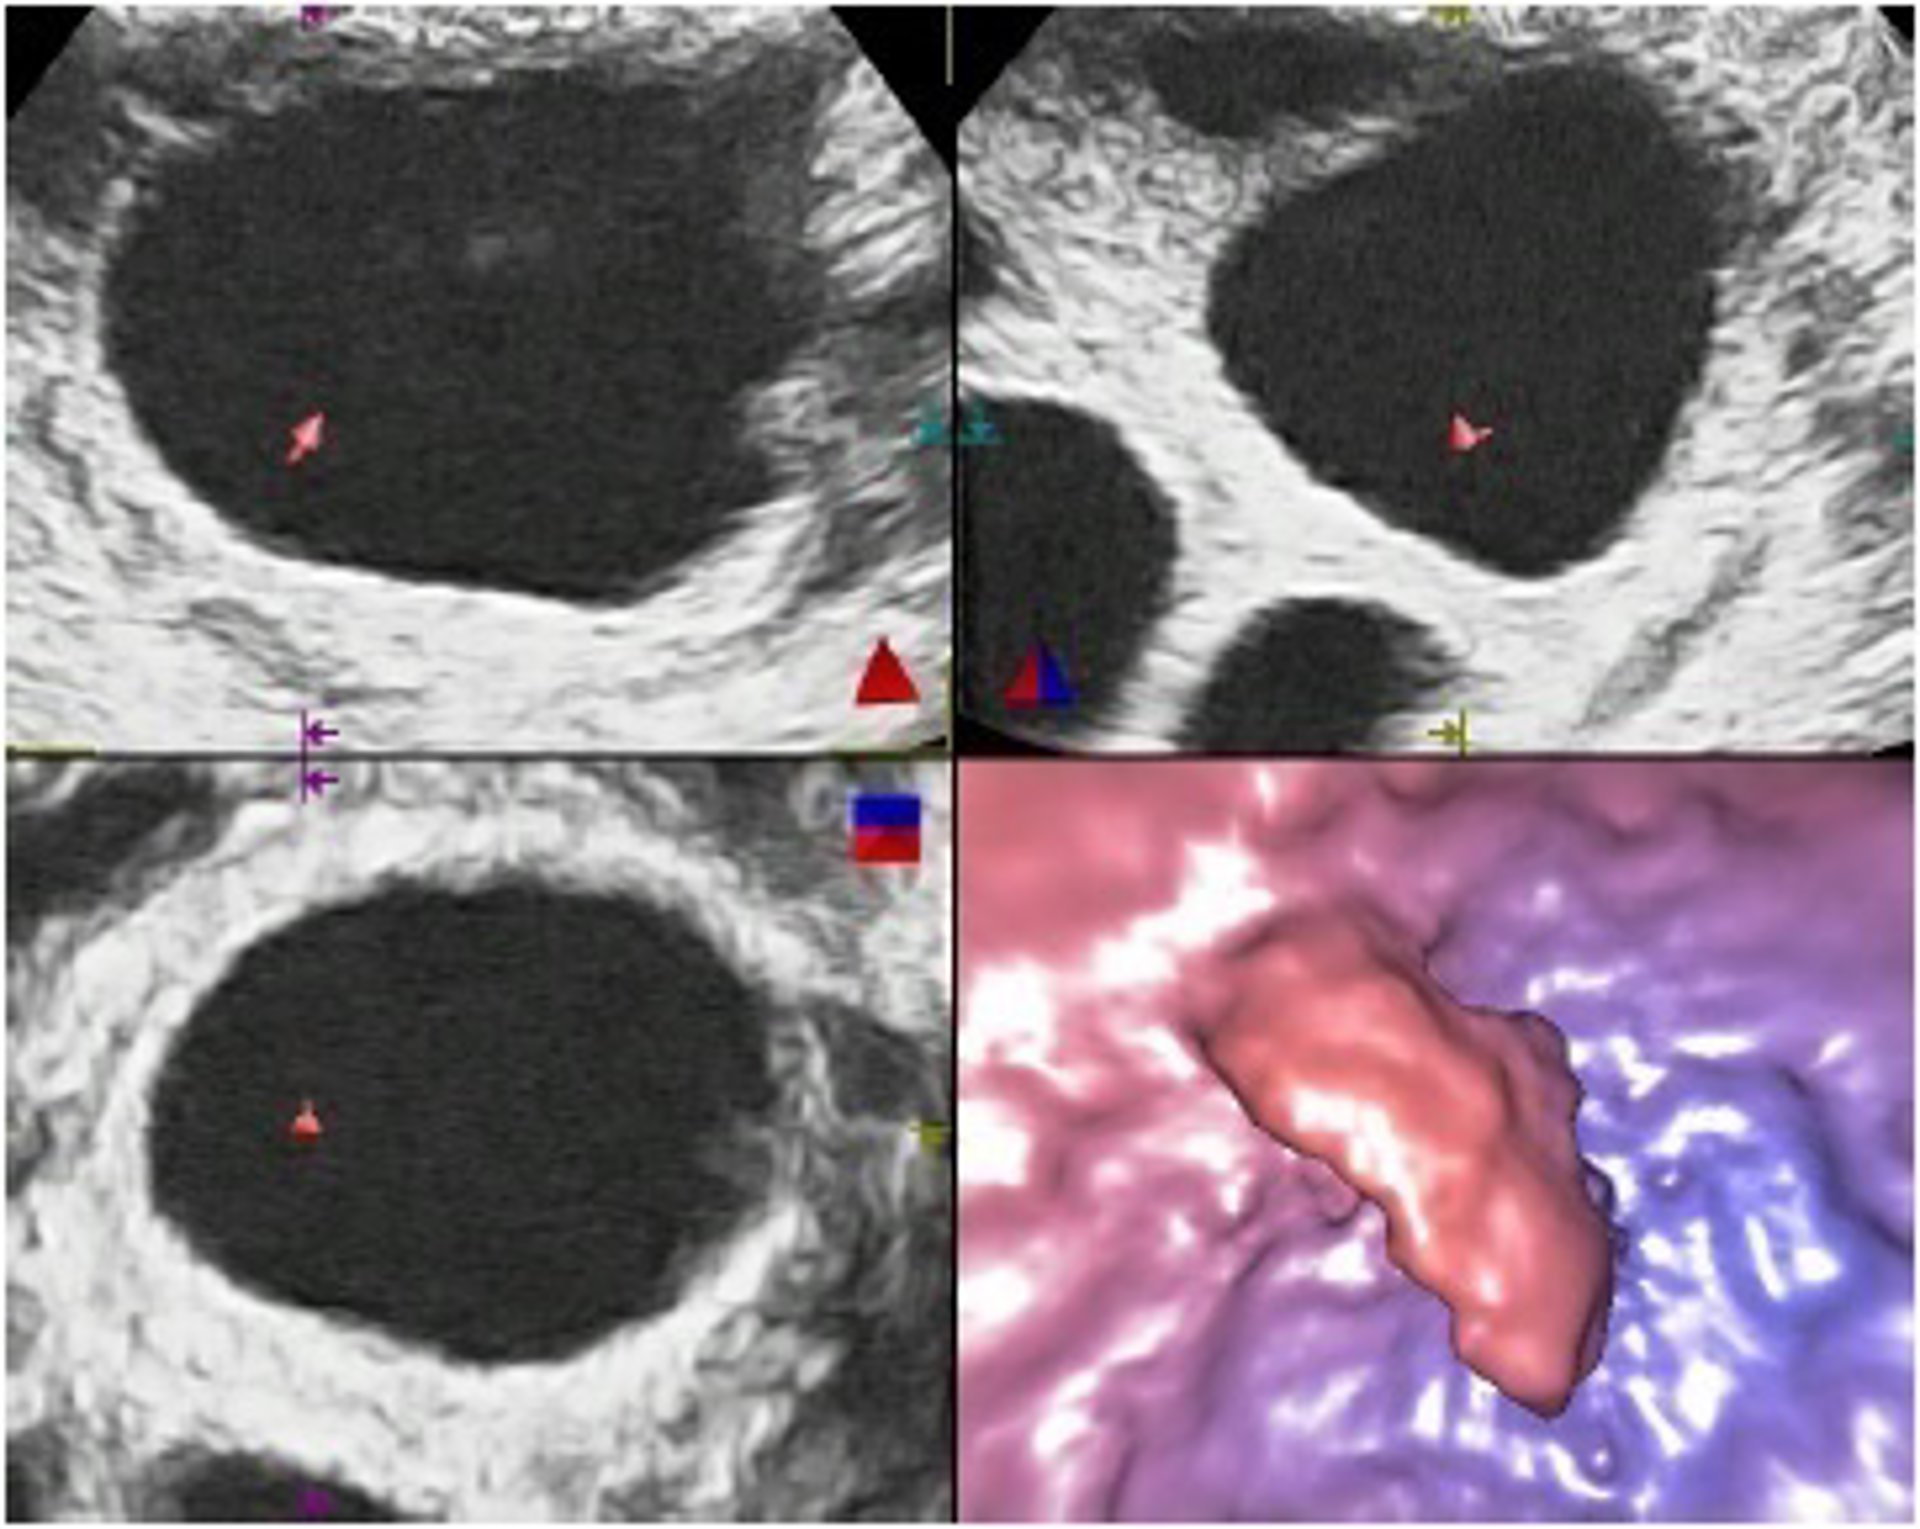

Foliculoscopia virtual

Un equipo de investigadores de la Universidad de Granada y de la Clínica Margen de esta ciudad ha dado a conocer una nueva técnica, denominada Foliculoscopia virtual, que permite saber si hay óvulos, y cuántos, antes de proceder a una punción de ovarios en los tratamientos de fecundación in vitro.

La nueva técnica de imagen médica permite predecir el número de óvulos que se podrán obtener mediante la punción de ovarios. De esta manera, la punción sólo se realizará en aquellos casos en los que se ha confirmado la existencia de óvulos, evitando los inconvenientes de todo tipo, físicos y emocionales, y los gastos innecesarios que se producen actualmente cuando la punción no tiene éxito, según detalla en una nota la clínica.

Los folículos son cavidades presentes en los ovarios en las que se desarrollan los óvulos y se pueden visualizar mediante un examen ecográfico. Para la fecundación in vitro se utilizan tratamientos hormonales que aumentan el número de los folículos y estimulan su crecimiento. En teoría, cada folículo tendría que contener un óvulo.